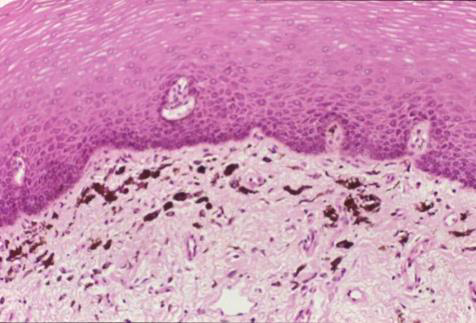

| 黑色素失禁(melanin incontinence): basal cell 可能破損 → macrophage 於 CT 吞噬 → melanophage  |